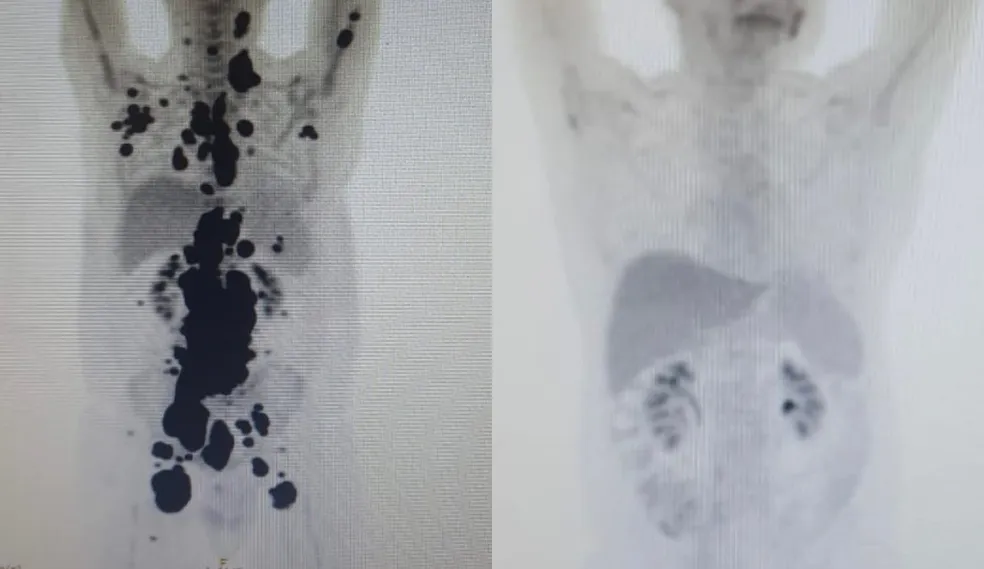

As duas imagens do Pet Scan (tomografia feita com um contraste especial ) (veja acima) representam “dois Paulos”: a da esquerda, o paciente que tinha como caminho único os cuidados paliativos, quando a alternativa é dar conforto, mas já sem expectativa de cura, e a da direita, um paciente com um organismo já sem tumores após o CAR-T Cell.

“Foi uma resposta muito rápida e com tanto tumor. Fico até emocionado [ao ver as duas ressonâncias de Paulo]. Fiquei muito surpreso de ver a resposta, porque a gente tem que esperar pelo menos um mês depois da infusão da célula. Quando a gente viu, todo mundo vibrou. Coloquei no grupo de professores titulares da USP e todo mundo ficou impressionado de ver a resposta que ele teve”, comemorou Vanderson Rocha, anteriormente sobre os exames de Paulo.